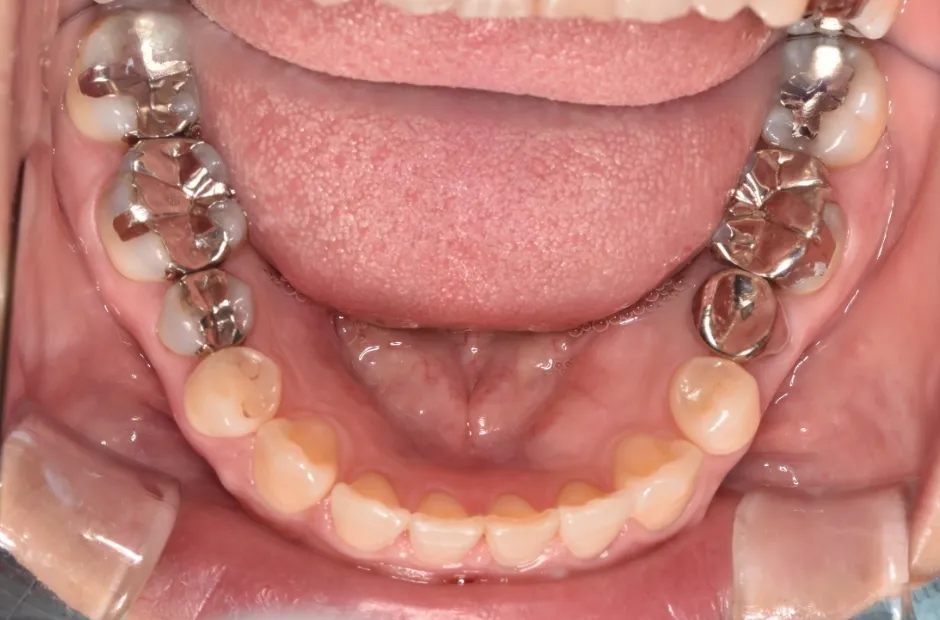

叢生

| 診断名・主訴 | 叢生 |

|---|---|

| 年齢・性別 | 43歳・女性 |

| 治療期間・回数 | 2年7か月 27回 |

| 治療に用いた主な装置 | 舌側矯正 |

| 抜歯部位 | 両顎4,4 |

| 治療費 | 100万円(税抜) |

| リスク・副作用 | 装置による違和感・疼痛・歯肉退縮・歯根吸収・虫歯のリスクなど |

治療中